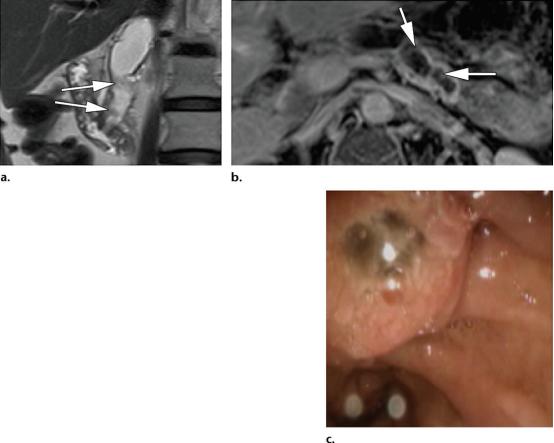

53岁男性,主胰管的导管内乳头状粘液性肿瘤,(a图)冠状位T2WI,示扩张的主胰管内低信号的充盈缺损影(白色长箭头),(b图)轴位增强T1WI示沿着扩张主胰管走形的结节样黏膜强化影(白色长箭头),(c图)内镜示十二指肠区域经典的鱼眼样外观,十二指肠大乳头突入十二指肠。